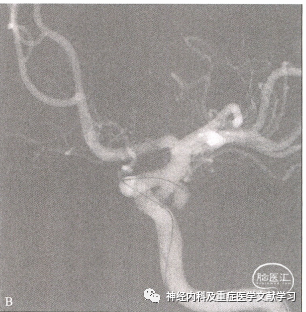

ICA交通段动脉瘤的血管内治疗与其他起源于颈动脉侧壁的动脉瘤相类似,可以采用支架或球囊等辅助栓塞。通常选取标准导引导管和微导管作为通道,将头端塑形的微导管送入动脉瘤腔内,并为递送弹簧圈提供一个稳定的通道。当从已填塞完毕的弹簧圈团中撤回头端成形的微导管时需要加倍小心,特别是宽颈动脉瘤,此时弹簧圈可能被拉入载瘤动脉中从而导致血栓形成。尽管在动脉瘤破裂情况下,必须平衡血栓栓塞和EVD部位颅内出血的风险,但如果弹簧圈已明显突入ICA腔内,则需使用支架将其固定于血管壁上(图1)。

图1 瘤顶分叶的复杂PComA动脉瘤(A),SAH,微导管只能栓塞其中一叶(B),因此更适合手术夹闭。